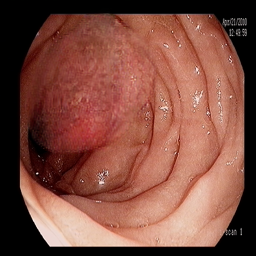

The performance metrics for Edgeconnect and AOTGAN on the validation data after fine-tuning the models, are shown in Table II. In addition to qualitative evaluation, Figure 3 provides example data from the different steps of the PolypConnect pipeline using the EdgeConnect model and the AOTGAN model. Due to obvious visual differences in the generated polyps between the models, we selected the EdgeConnect model as the main polyp inpainting model of the PolypConnect pipeline for further evaluation and qualitative assessment by domain experts.

Figure 3: Sample data used and generated in the different steps of PolypConnect pipeline. (a) - real polyp images, (b) - manually annotated polyp masks, (c) - randomly selected colon images used as input to the final step of PolypConnect, (d) - extracted edge images of row c. (e) - extracted edge images of polyp regions of row a using the masks of row b. (f) - combined edge images of row d and f. (g) - generated polyp on the images of row c using EdgeConnect. (h) - generated samples from AOTGAN.